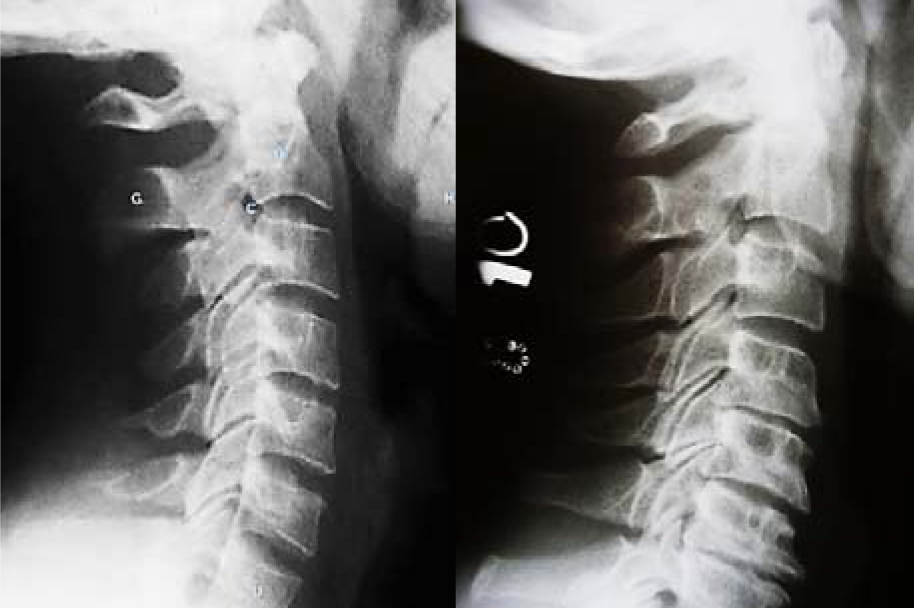

สามารถวินิจฉัยได้จากการซักถามประวัติและตรวจร่างกายโดยแพทย์ แต่ถ้าอาการปวดเป็น มากขึ้นอย่างรุนแรง หรือรักษาเต็มที่แล้วอาการไม่ดีขึ้น อาจจําเป็นต้องเอกซเรย์กระดูกสันหลัง หรือเอกซเรย์คลื่นแม่เหล็กไฟฟ้าถ้าสงสัยภาวะกระดูกสันหลังกดทับเส้นประสาท